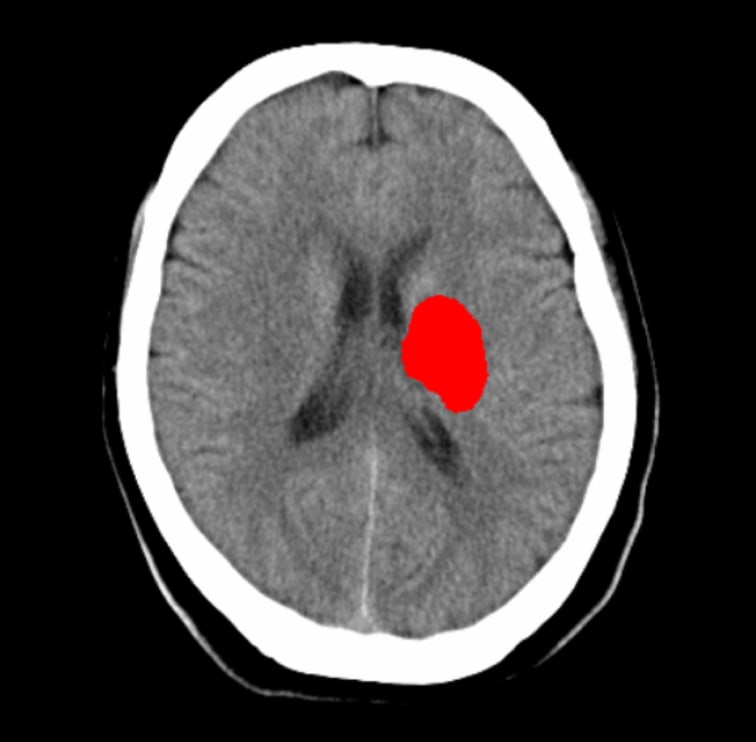

通常読影後に以下いずれかの抽出結果を参照できます

- 高吸収領域の表示

- 高吸収、低吸収、不明瞭領域の表示

- 頭部単純CTの画像情報から頭蓋内の高吸収・低吸収領域を抽出し強調表示をします

- 頭蓋内で前後のスライス及び同一スライス内の左右で比較して組織構造もしくは組織境界の不明瞭化が見られる領域を表示します

- 抽出領域がセグメンテーション表示されることで視覚的な確認が可能です